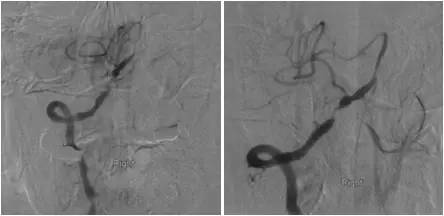

DSA:右侧椎动脉V4段重度狭窄,前向血流减慢,基底动脉近中段未见顺行显影,左侧椎动脉V4段远心端闭塞,右后交通动脉开放,经右颈内动脉造影可见基底动脉中远段显影,左胚胎型大脑后动脉(图3-5)。

图3

图4

图5